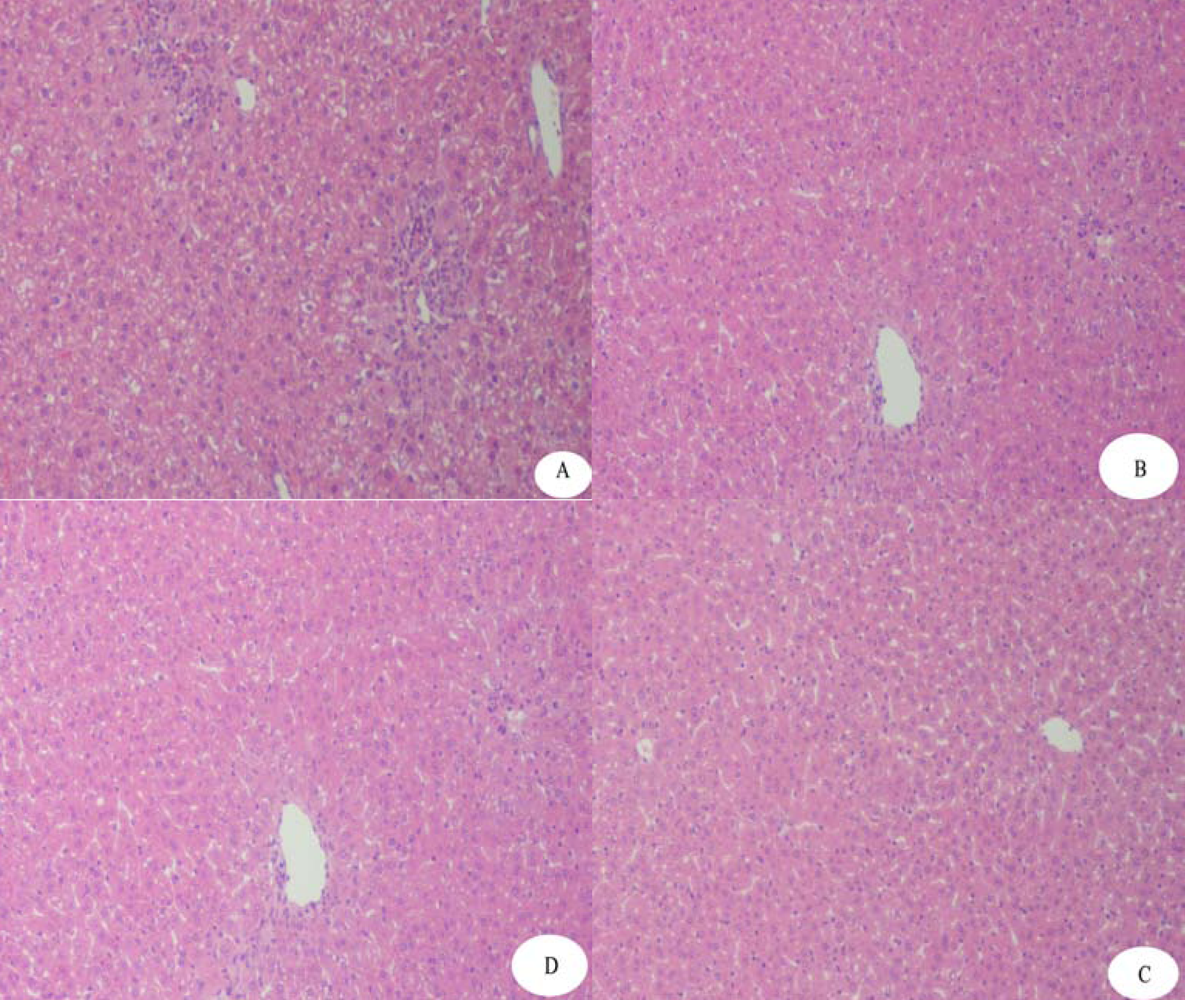

4.5. Protective Effects of rAPSL against Mice of Acute Hepatic Injury Induced by CCl4 or AAP